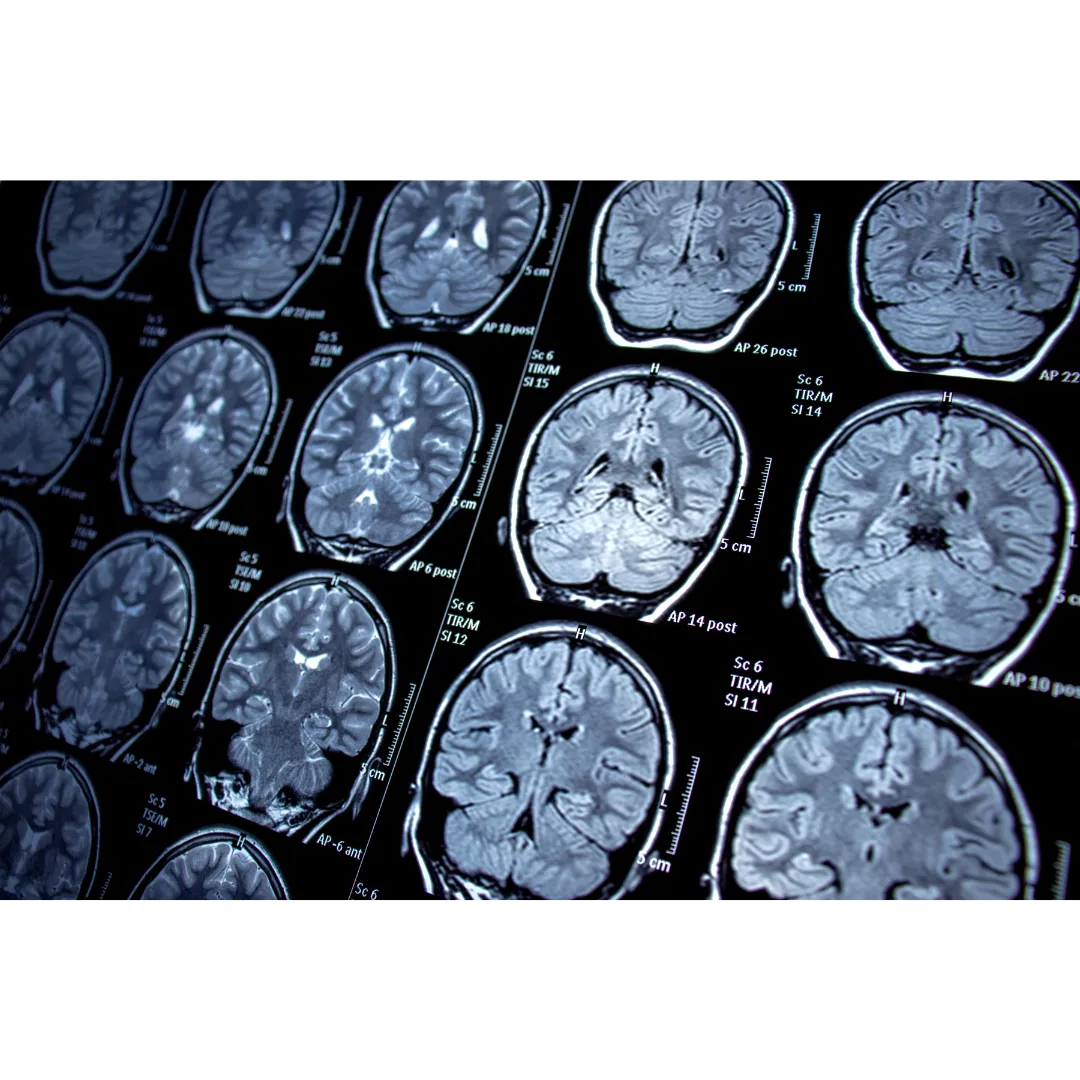

Cognitive deficiencies refer to impairments in mental processes such as memory, attention, reasoning, and problem-solving, often caused by conditions like traumatic brain injuries, stroke, or neurodegenerative diseases. Hyperbaric Oxygen Therapy (HBOT) can help by increasing oxygen delivery to the brain, which improves circulation and supports the repair of brain cells. The therapy also stimulates neuroplasticity, allowing the brain to form new connections and reorganize itself to regain cognitive function. Additionally, HBOT reduces brain inflammation, a common factor in cognitive decline, and promotes the growth of new blood vessels, further enhancing brain health. These combined effects can improve memory, focus, and mental clarity, offering significant benefits for those with cognitive deficiencies.

HBOT involves breathing pure oxygen in a pressurized chamber, which increases oxygen delivery to the brain and promotes neuroplasticity—the brain’s ability to form new connections. Key benefits for ADHD include:

Neurological disorders affect the brain, spinal cord, and nervous system, leading to conditions such as migraines, multiple sclerosis, Parkinson’s disease, and epilepsy. These conditions often involve inflammation, oxidative stress, and impaired neuronal function. HBOT is emerging as a supportive therapy to enhance neuroprotection and improve quality of life.

HBOT aids neurological recovery and function by:

Enhancing Brain Oxygenation: Promotes neural repair and function.

Reducing Inflammation: Alleviates inflammation-related symptoms in neurological disorders.

Supporting Cellular Energy Production: Improves mitochondrial function for sustained brain health.

Stimulating Neurogenesis: Encourages the formation of new brain cells and connections.